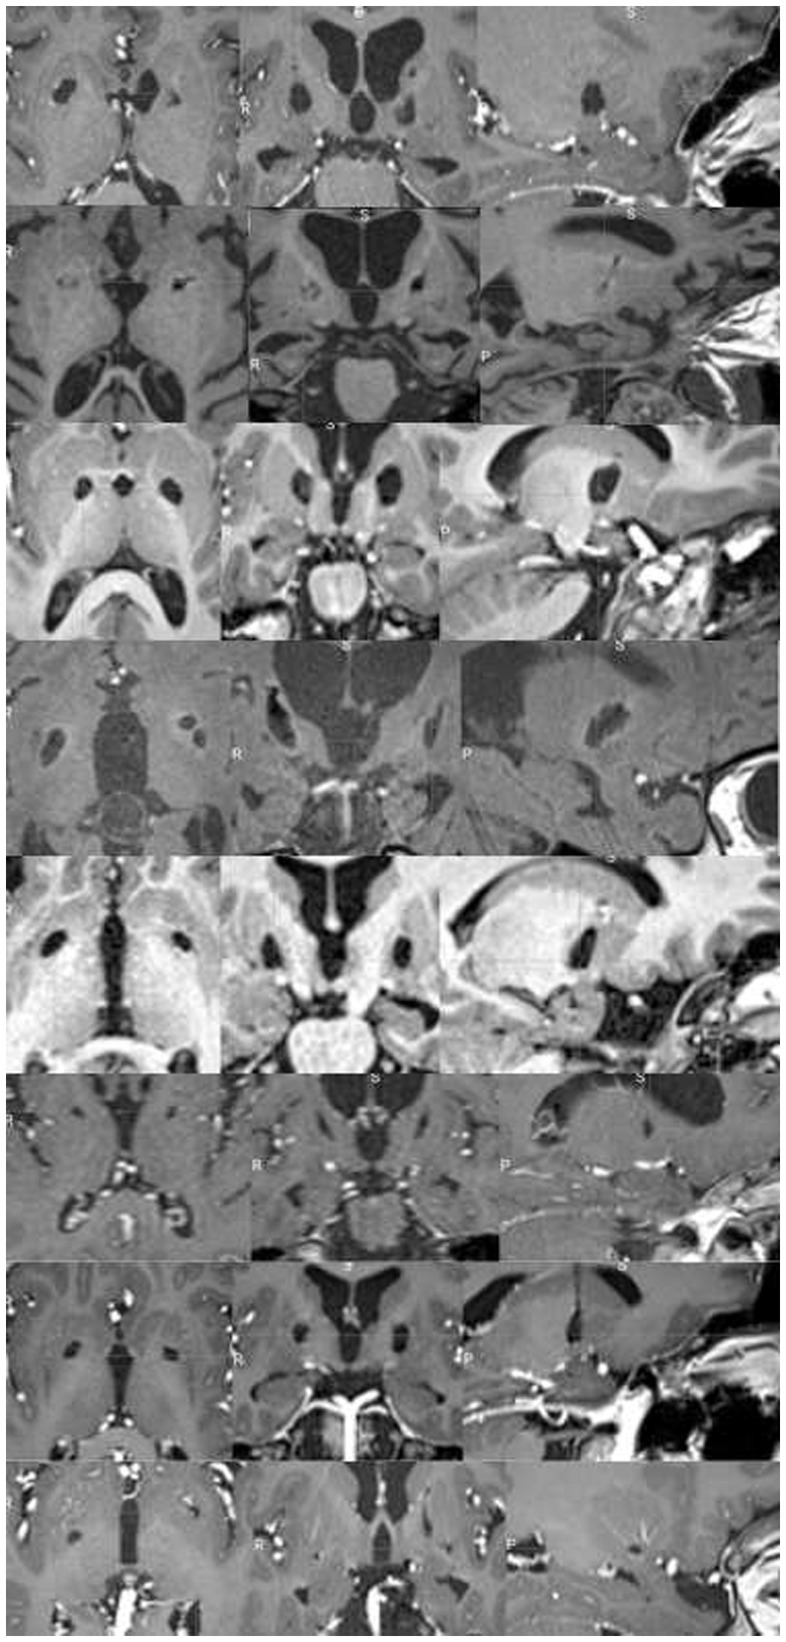

In all patients undergoing late MRI, RP lesion was still visible on both sides (Figure 5), including in the three patients who underwent re-pallidotomy for lesion extension.

Figure 5

Chronic evolution of GPi lesions in subject undergoing late MRI scans. Each rows represent a single patient T1-weighted MRI sequence on axial, coronal, and sagittal view (from up to bottom: patient #1, #5, #7, #8, #14, #15, #17, #18). In all patients, bilateral lesion was still visible.